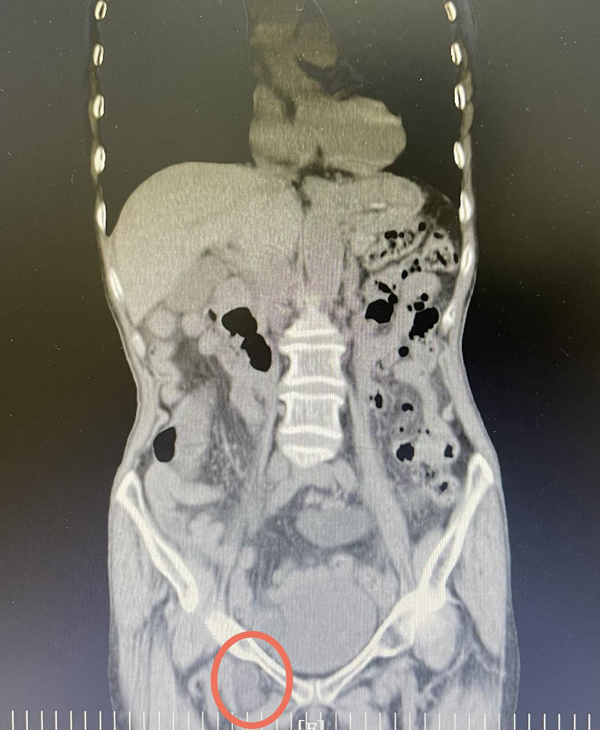

主管的于洁副主任医师详细询问病史,仔细查体后发现患者右侧腹股沟韧带下方似可触及一质软肿物,结合症状体征,考虑闭孔疝嵌顿可能,右髋部疼痛是因为疝压迫闭孔神经所致,肠梗阻系肠管嵌顿引发,下腹部CT结果回报证实了判断。于洁副主任医师当机立断,立即安排急诊手术,术中发现右侧闭孔疝形成并小肠嵌顿,嵌顿肠管颜色暗红,并见点状瘀斑,给予温盐水湿敷处理后肠管机能改善,随后成功进行疝修补术。术后,在普外一科全体医护人员的悉心照顾下王奶奶顺利恢复,术后1周出院。

“闭孔疝”是指腹腔内脏器或组织连同腹膜壁层离开正常的解剖位置,经过髋骨闭孔向股三角区突出的腹外疝。发病多为消瘦老年妇女,故也被称为“小老太太疝”。发病率占疝发病率的0.05%~0.07%,非常罕见,发病隐匿,所以疝嵌顿绞窄肠坏死率高达25%~90%。